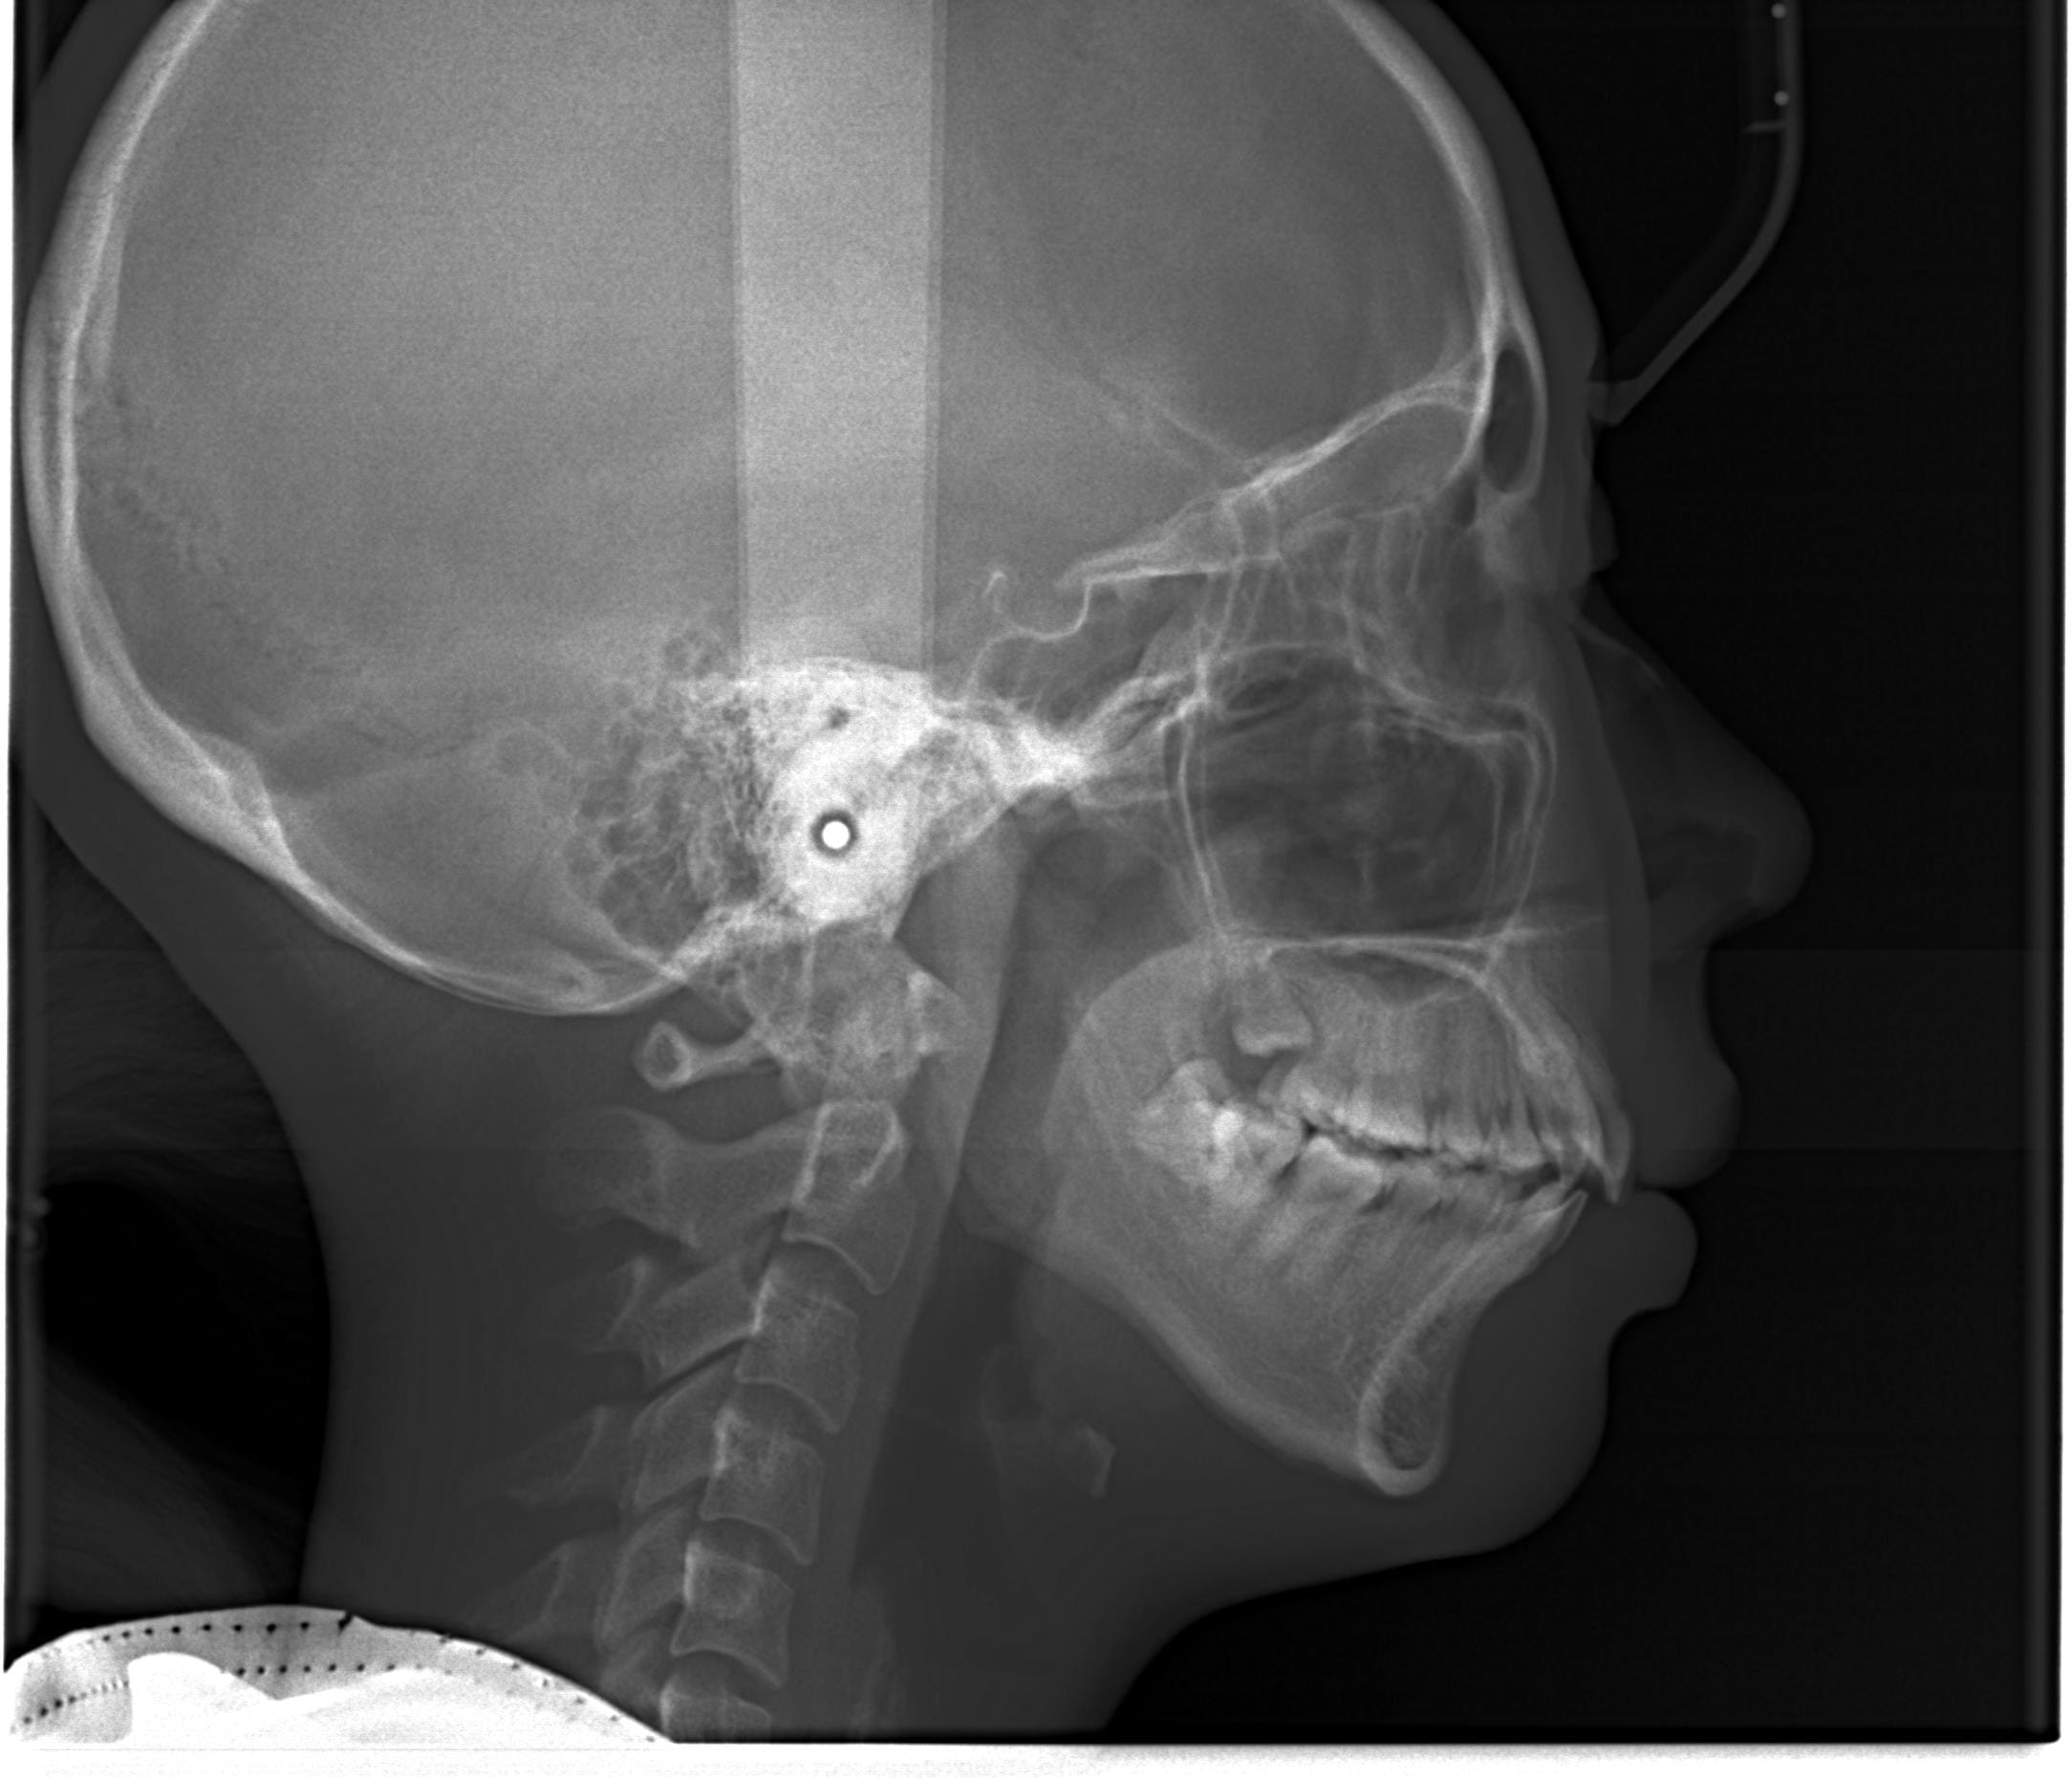

| 年齢・性別 | 21歳 |

|---|---|

| 主訴 | 叢生が気になる・前歯に埋伏歯がある |

| 治療期間・回数 | 6ヶ月 |

| 費用 | 935,000円 |

| 上顎の左側3番が埋伏していたため、上顎左右の3番および親知らずを抜歯し、矯正治療を行いました。 治療開始からおよそ6ヶ月で歯列が整い、審美的にも機能的にも良好な結果が得られた症例です。 |

レントゲン撮影、口腔内の写真撮影などにより、くわしくお口の状態を確認します。また、むし歯や歯周病など治療が必要な歯がないかの確認もさせていただきます。